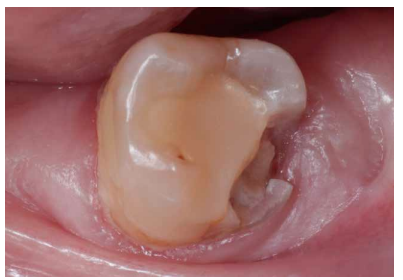

La paciente no presentaba antecedentes médicos de interés. En la exploración clínica (Figura 1) se observó que el 3.7 presentaba una lesión cariosa extensa, correspondiendo a un valor ICDAS 6, y una restauración oclusal previa de composite. En la exploración radiográfica (Figura 2) no se apreciaba banda de dentina entre la lesión cariosa y la cámara pulpar. Por tanto, según la clasificación clínico-radiográfica del International Caries Classification and Management System (ICCMS®) 4 se considera una lesión de caries severa. Presentaba un ligero ensanchamiento del espacio del ligamento periodontal en la raíz mesial y lesión apical. Se realizaron las pruebas de diagnóstico pulpar y periapical pertinentes (Tabla 1). El diagnóstico pulpar fue pulpitis irreversible sintomática y el diagnóstico periapical fue periodontitis apical sintomática.